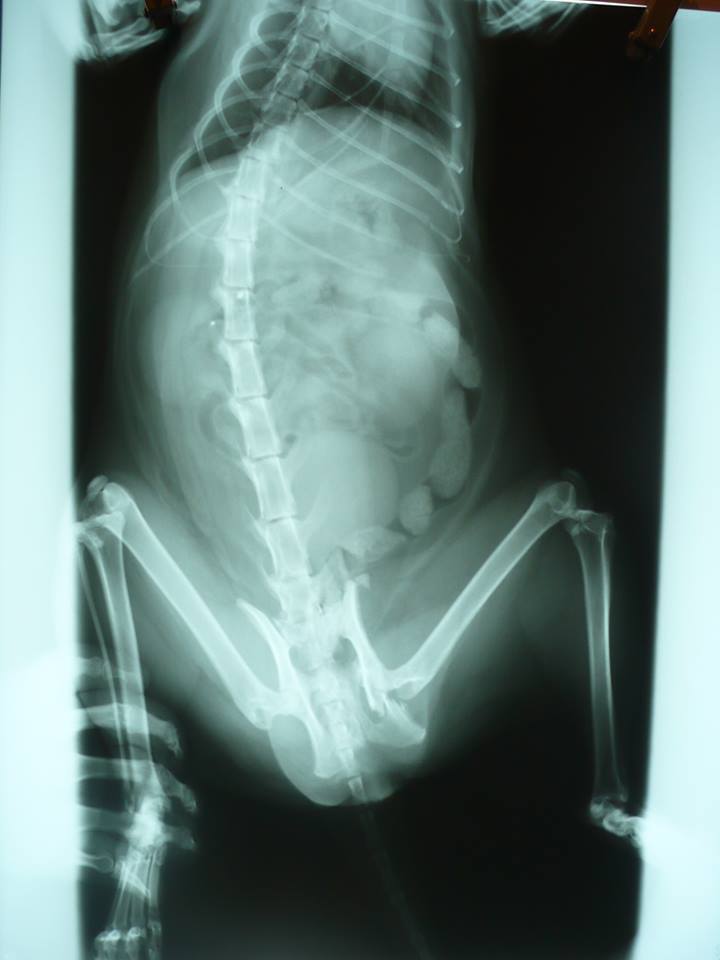

主題: 被車碾過骨盆斷裂 申請者姓名: 陳曉霏 花色: 申請日期: 2013-08-23 07:05:09 申請者部落格: 申請者臉書網址: http://www.facebook.com/xiaofeic 所在縣市/合作醫院: 台北市/極光動物醫院 治療費用: 27045元 需求人數: 29人 已結案 (2013-09-19 17:55:36) 報名人員: Cathy.H(已付款)、Yuri Chang(已付款)、grace0710(已付款)、Lilo Hsueh(已付款)、虎咪(已付款)、沈明明(已付款)、peggy(已付款)、Nancy Chiou(已付款)、FiFi(已付款)、Ekim Lu(已付款)、陳曉霏(已付款)、李昭慧(已付款)、Annisui Strauss(已付款)、王千枝(已付款)、周 昊暵(已付款)、哇咧蹦 x14(已付款)、 候補人員: 動物病情說明: 路上看到一隻貓躺著不能動

請醫生檢查後 骨盆的地方有斷

疑似躺在車下睡覺 被壓過去

前腹側還有一個滿大的疝氣

才會整個被碾過去動物近況說明: 目前骨盆處骨頭還在修復中